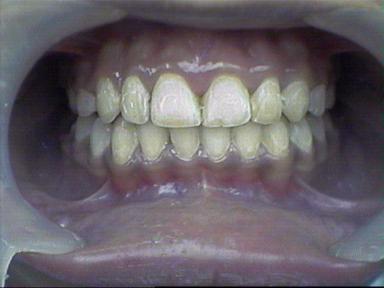

Malocclusion [Div.II]

Before Treatment Intra Oral